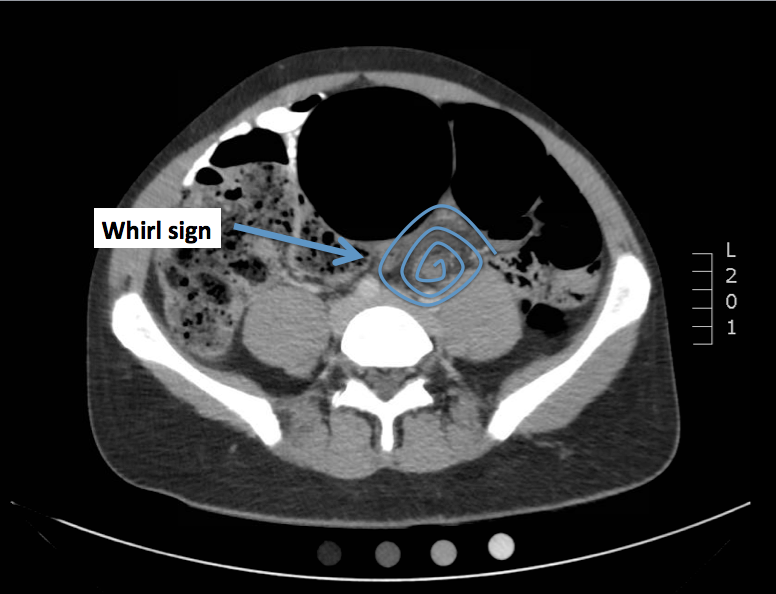

Emergency Medicine Visual Diagnosis Diagnosis Sigmoid Volvulus Define Medical Term Volvulus Volvulus causes obstruction to the flow of contents and threatens occlusion of the supplying blood. Volvulus is the twisting of a section of the large or small intestine (bowel). Symptoms include abdominal distension, pain,. It is a serious condition that may. Volvulus occurs when part of the intestine loops around and folds over itself. Twisting of a loop of intestine.. Define Medical Term Volvulus.

Volvulus of the Gastrointestinal Tract Appearances at Multimodality Define Medical Term Volvulus Symptoms include abdominal distension, pain,. Volvulus is the twisting of a section of the large or small intestine (bowel). It often happens in the cecal and sigmoid colon sections of the. It is a serious condition that may. Volvulus causes obstruction to the flow of contents and threatens occlusion of the supplying blood. Volvulus is a condition that occurs when. Define Medical Term Volvulus.